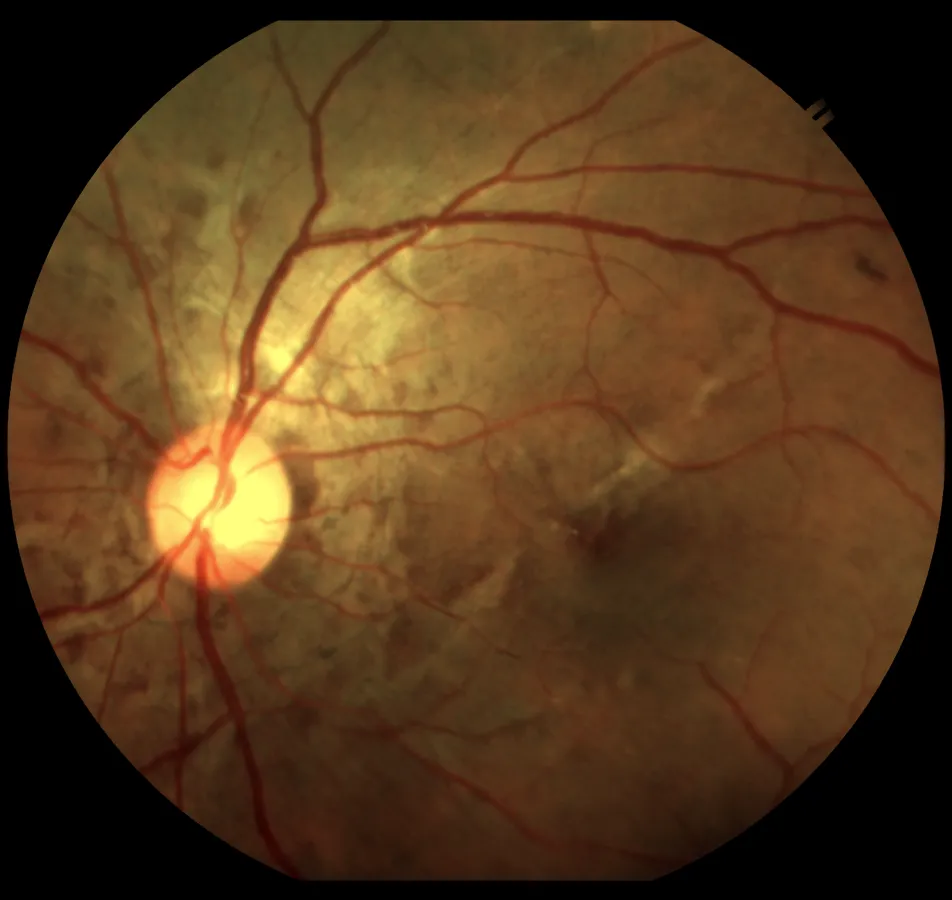

This intensive hands-on program is designed to provide ophthalmologists with focused exposure to the fundamentals and practical aspects of Medical Retina. The course integrates imaging, lasers, and intravitreal procedures with case-based learning, enabling participants to build confidence in diagnosis and management of common and complex retinal conditions.

TSA serves a large and diverse patient population, enabling fellows to experience the complete range of retinal diseases from common diabetic retinopathy and age-related macular degeneration to rare inherited retinal disorders. Continuous exposure to outpatient and inpatient cases sharpens diagnostic and clinical decision-making.

Fellows are trained in advanced diagnostic modalities (OCT, FA, ICGA, widefield imaging, OCT angiography) and get hands-on experience with retinal lasers, intravitreal injections, and opportunities to assist or perform vitrectomies under expert guidance.

• Clinical training- Supervised participation in Retina OPD with exposure to diverse retinal pathologies including diabetic retinopathy, ARMD, Retinal vascular occlusions, Uveitis-related retinal disorders etc

• Diagnostic skills & interpretation: Interpretation of advanced retinal imaging modalities like OCT, OCT-A, FFA, B-scan.